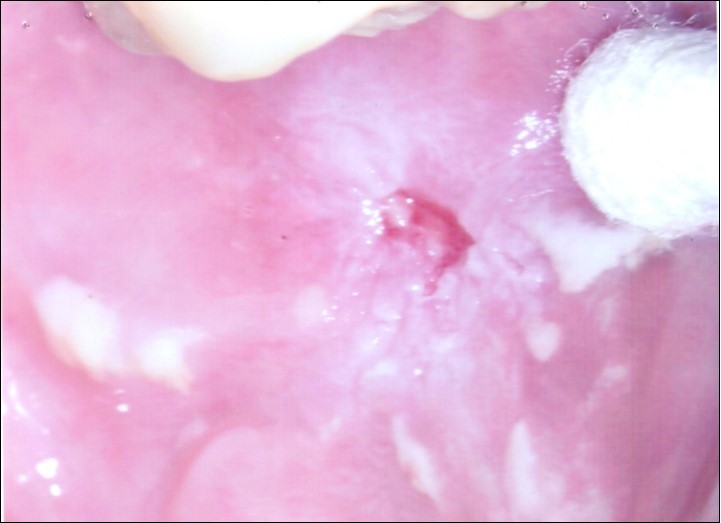

Repeat colposcopy was performed after 6 weeks. This revealed a small ulcerated area at the site of previous biopsy with rolled healing edges, and a separate small ulcer at the 12 o’clock position. (Figure 2a, Figure 2b, Figure 2c) Careful inspection of the buccal mucosa revealed similar ulcers in the left buccal region. (Figure 3)

Figure 2c.Repeat colposcopy (high magnification)